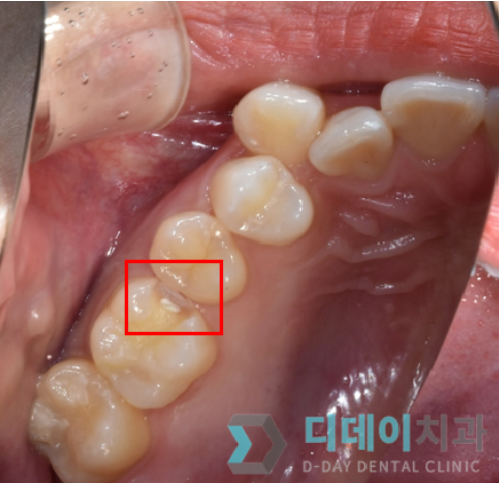

검진하니 말씀하신 대로 어금니에 충치가 있었습니다.

(아래 사진으로 까만 작은 구멍 보이시나요?)

강남충치치료

사진보다 실제로 보면 치아 부식이 심했고 통증도 심하셨습니다.

검진을 진행한 후, 인레이로 충치 치료를 하기로 했습니다.